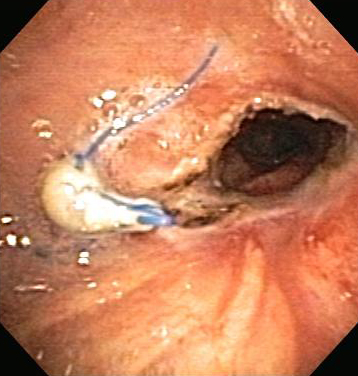

Post-lung transplant anastomotic bronchial stenosis: right mainstem anastomosis post-multimodal endoscopic therapy

From the collections of Jose Fernando Santacruz MD, FCCP, DAABIP and Erik Folch MD, MSc; used with permission